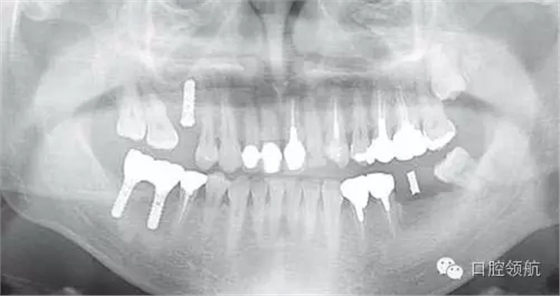

圖2是右側(cè)種植體植入后,左下磨牙缺損部診斷用導板戴用時的曲面斷層影像。拔牙后6個月,在預定植入部位有若干不透明的影像。

圖2 左下磨牙缺損部植入前的曲面斷層影像。